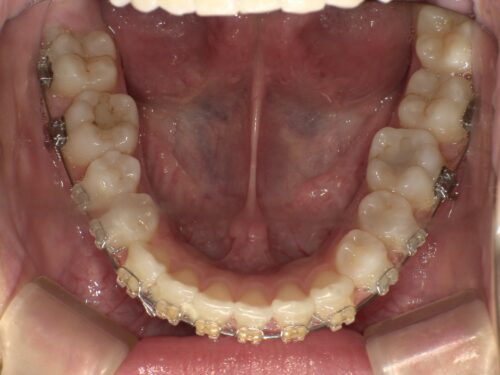

ワイヤー装着後・上顎の写真

上顎に装置とスクリューが装着された状態

上の前から4番目の歯を抜歯し、上顎に入れたスクリューとワイヤーを繋いで、前歯を後ろに引っ張っていきます。これが今回の治療のポイントになります。